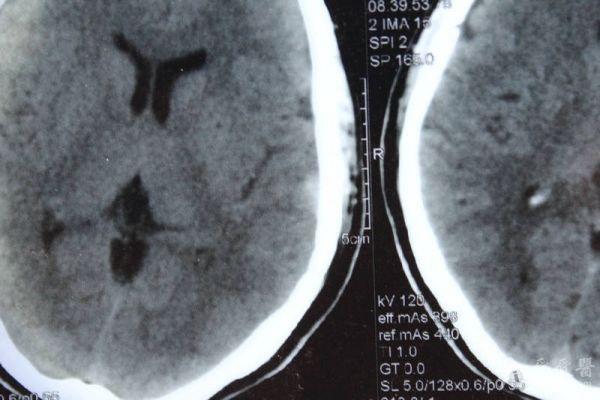

脑部占位病变CT,MRI图片,请帮忙诊断

最近感图样,无其它脑病病史

考虑脑膜瘤!!

磁共振没有平扫,增强矢状位没找到病灶。像脑膜瘤。

图片不是很清楚,应该是脑膜瘤!